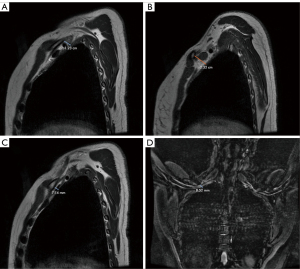

Magnetic resonance imaging (MRI), magnetic resonance angiography (MRA), and magnetic resonance venography (MRV) were performed using the NeoVista system (Sunnyvale, CA, USA) with the arms in both abducted and neutral positions. Evaluation of the right-side demonstrated a 12-mm gap at the level of the brachial plexus with the arms abducted (Figure 1A). On the corresponding image obtained with the arms in the neutral position, this gap increased to 23 mm (Figure 1B). A 7-mm gap between the first rib and the clavicle at the level of the brachiocephalic vein was observed on the right with the arms abducted (Figure 1C). Sagittal imaging in abducted position revealed marked hypertrophy of the middle scalene muscle with narrowing of the scalene triangle. Coronal Short Tau Inversion Recovery (STIR) sequences demonstrated an approximately 8mm gap at the level of the brachial plexus with the arms abducted (Figure 1D). There was no evidence of pectoralis minor compression. Cervical spine MRI demonstrated no significant disc degeneration.